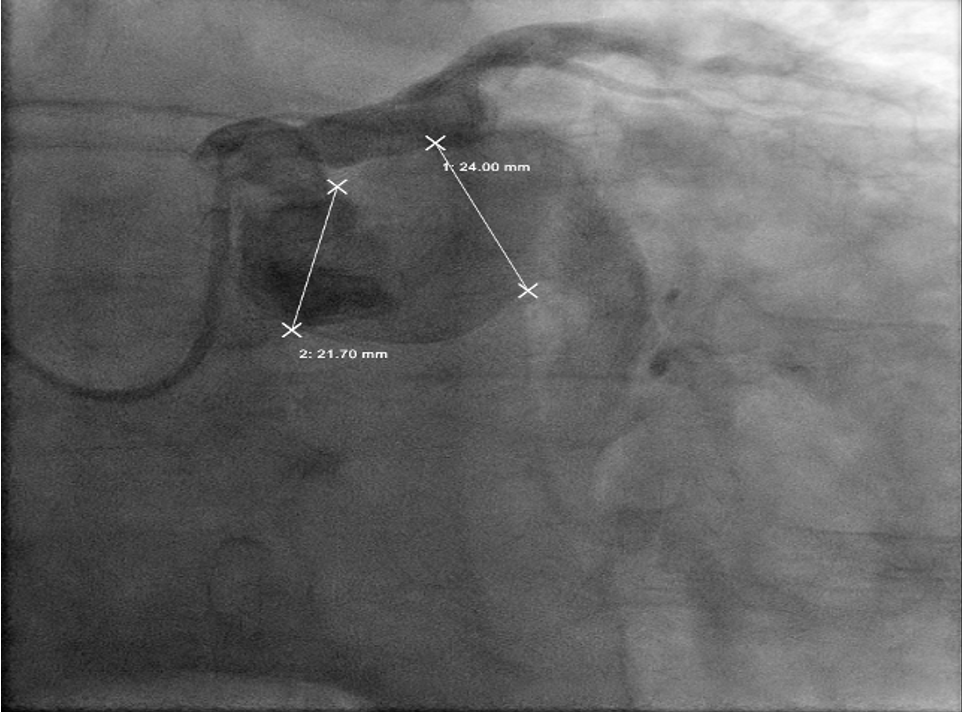

The angiogram revealed multivessel giant coronary aneurysms. The left anterior descending (LAD) coronary artery had an 11 mm proximal-to-mid artery long aneurysm involving the first diagonal branch (Figure 1). The circumflex artery had a proximal giant aneurysm measuring 24 mm, with very little visualization of distal vessel (Figure 2). Coronary dye was mostly stagnant in the coronary aneurysm, which did not fill distal vessels well. The right coronary artery (RCA) had the largest giant aneurysm, measuring 45 mm, with an inability to fill any distal vessels (Figure 3).